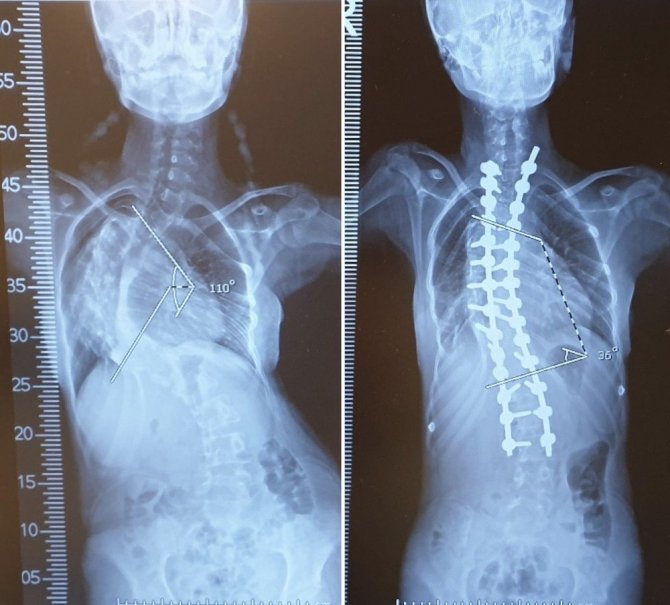

Omurgasındaki 110 derecelik eğrilik nedeniyle yürümekte zorlanan ve hayatında büyük güçlükler çeken Medine Şengül, tedavi için VM Medical Park Mersin Hastanesine başvurdu. Yapılan kontroller sonucunda skolyoz ameliyatı olması kararı alınan hasta, Ortopedi ve Travmatoloji Uzmanı Prof. Dr. Mustafa Çeliktaş ve ekibinin katıldığı 5 saat süren operasyon sonucunda omurgasındaki eğrilik giderilerek sağlığına kavuştu.

Başarılı bir şekilde sonuçlanan ameliyatın ardından açıklama yapan Prof. Dr. Mustafa Çeliktaş da "Hastamız Medine bize başvurduktan sonra yaptığımız tetkiklerde normalde düz olması gereken omurgasının yaklaşık 110 derece kadar eğrildiğini gördük. Hastalık oldukça ilerlemiş durumdaydı. Skolyoz hastalığını erken dönemde yakaladığımızda tamamen düzeltmek mümkün. Fakat ileri derece eğriliklerde amacımız hastanın zarar görmesini engelleyerek kabul edilebilir seviyelere düşürmek. Medine hastamızda da bu eğrilik ameliyattan sonra büyük oranda düzeldi. Yaptığımız kontrolde omurgasındaki eğriliğin dışarıdan hiç fark edilmeyecek seviyeye geldiğini gördük. Skolyozda önemli olan hastalığın tanısının erken teşhis edilmesi ve erken tedavi edilmesi. Fakat geç yakalansa dahi yapılacak özellikli ameliyatlarla deformitenin önüne geçilebilmektedir" diye konuştu.